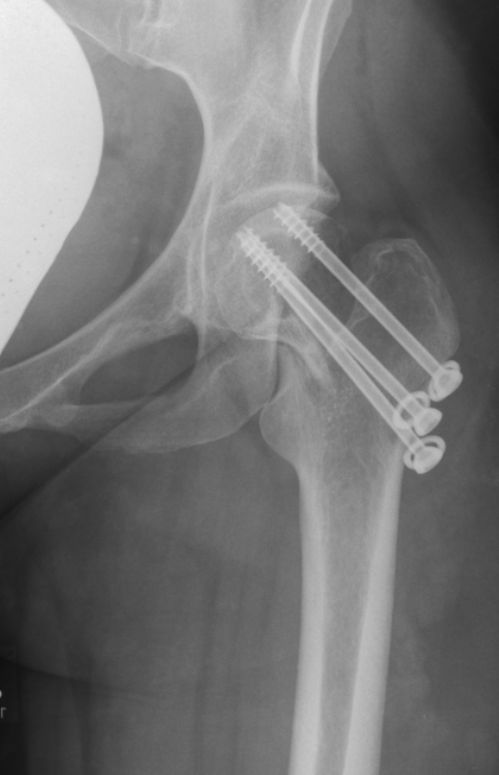

28-jährige Frau mit Spontanfraktur des linken Schenkelhalses. | |

| Bild in der Notaufnahme |

![]() | |